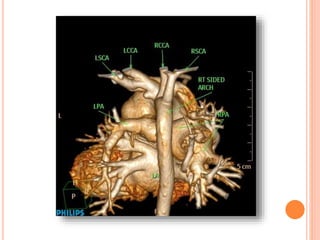

Case 3 35Days girl